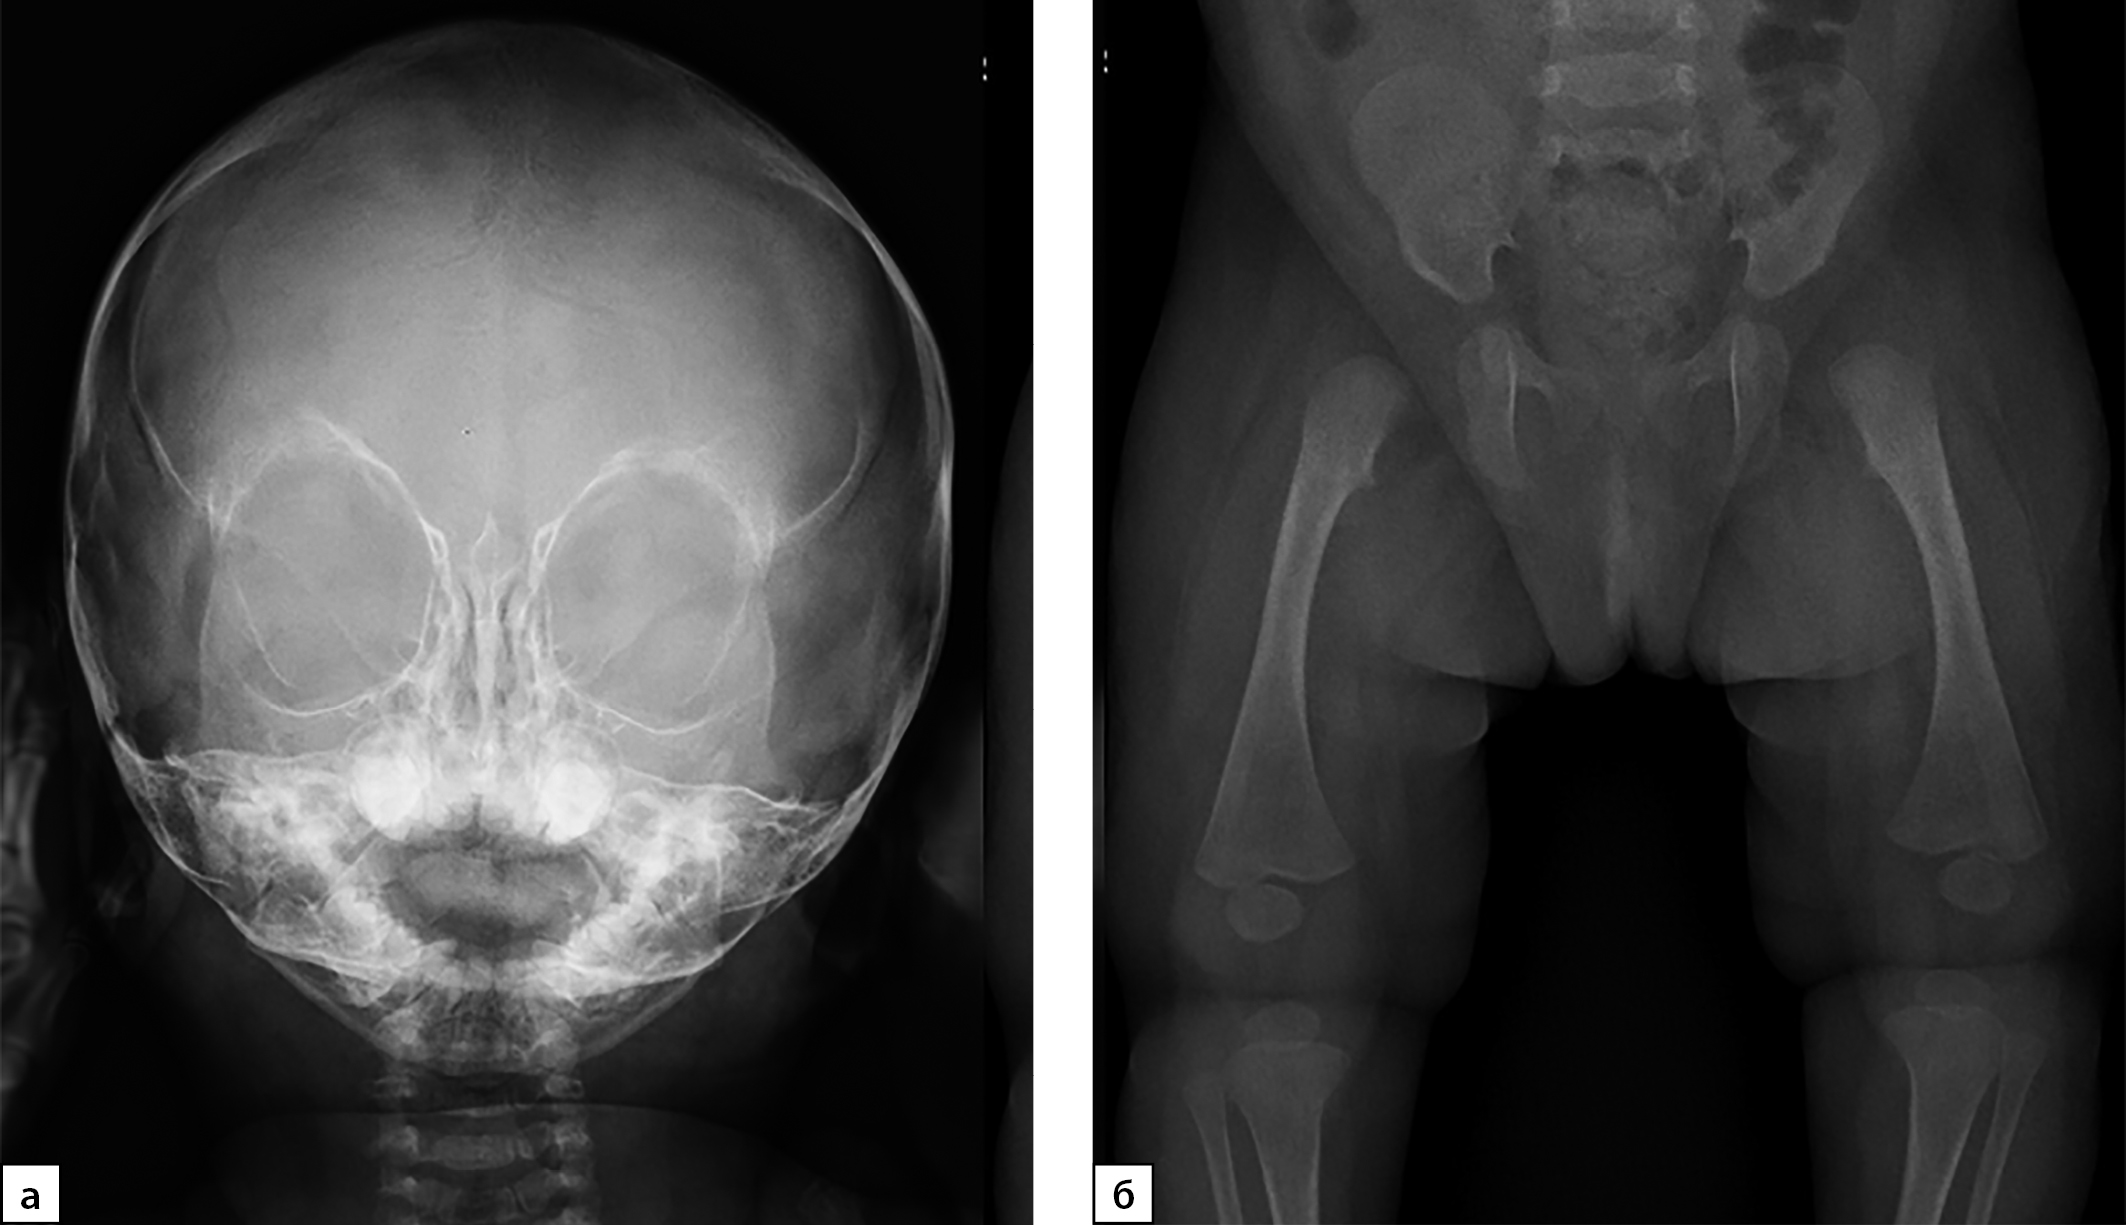

Рисунок 6. Пациентка №4, а — рентгенограмма черепа в прямой проекции. Вид лицевого скелета; б — тазобедренные суставы: гипоплазия костей таза. Проксимальные эпифизы бедренных костей не оссифицированы.

По данным рентгенографии и МСКТ, визуализированы расширенные большой и малые роднички и аномалии строения затылочной кости (рис. 5).

При осмотре ортопедом наблюдались сгибательно-разгибательные контрактуры пальцев кистей и лучезапястных суставов, резкое ограничение движений в лучезапястных суставах при нормальном объеме движений в локтевых суставах (табл. 2). Наряду с этим имелись сгибательные контрактуры в тазобедренных суставов и выраженные, около 150 градусов, сгибательные контрактуры в коленных суставах. На рентгенограмме таза и тазобедренных суставов нарушения соотношения и признаков асептического некроза выявлено не было (рис. 6).